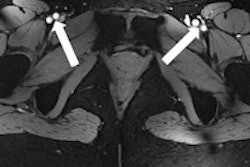

All these efforts culminated in images of the beating heart with a spatial resolution that is by a factor of five superior to that routinely available at 1.5 tesla, and which might come close to turning a 10-megapixel digital camera into a 50-megapixel digital camera. These improvements offer detailed insights into cardiac anatomy and allow accurate delineation of myocardial borders, a feature that is essential for cardiac chamber quantification.

Cine images (left: four-chamber view, middle: short-axis view, right: two-chamber view) of the beating heart acquired with a novel 16-channel transmit/receive radiofrequency coil array at 7.0 tesla with an in-plane resolution of 1 x 1 mm2 and a slice thickness of 4 mm. Images courtesy of Dr. Thoralf Niendorf.The novel technology tailored for cardiac MRI together with the quality of the anatomical and functional images have created excitement among the international imaging community during the ISMRM meeting, which ran a special session on ultrahigh-field CMR. The first clinical results and experiences are very much heartening and are the driving force for broader clinical studies.